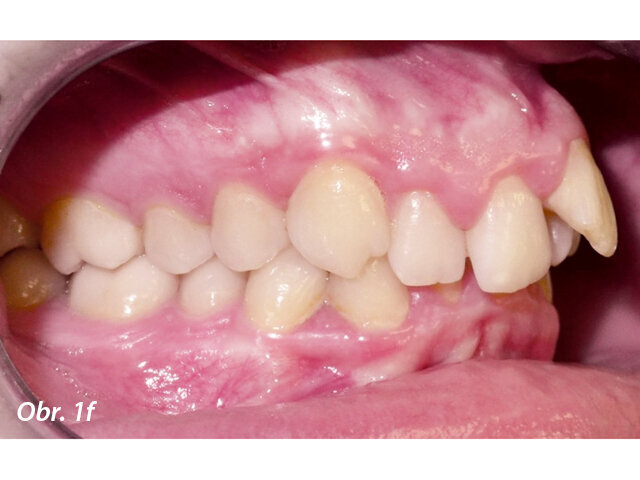

17letý chlapec přišel na konzultaci v prosinci 2014. Při intraorálním vyšetření bylo zjištěno: vztah molárů v I. třídě dle Anglea oboustranně a vztah špičáků v I. třídě vlevo a II. třídě vpravo. Šířka horního zubního oblouku v úrovni molárů byla normální, v místě premolárů však byl zubní oblouk výrazně zúžený a v mezišpičákové oblasti bylo výrazné stěsnání. V dolním zubním oblouku (úzký, tvar paraboly) bylo stěsnání s úplným deficitem místa pro zub 42, který byl v ektopické lingvální poloze. Hloubka skusu byla stoprocentní s traumatickým nákusem do gingivy v okolí dolních frontálních zubů. Zuby horního oblouku byly mírně větší než průměr, s malým nepoměrem Boltonova indexu. Objektivní extraorální vyšetření odhalilo syndrom dlouhého obličeje, vývoj střední třetiny obličeje byl normální a nazální pyramida byla široká ve spojení s mírnou mandibulární retruzí (obr. 1a–h).